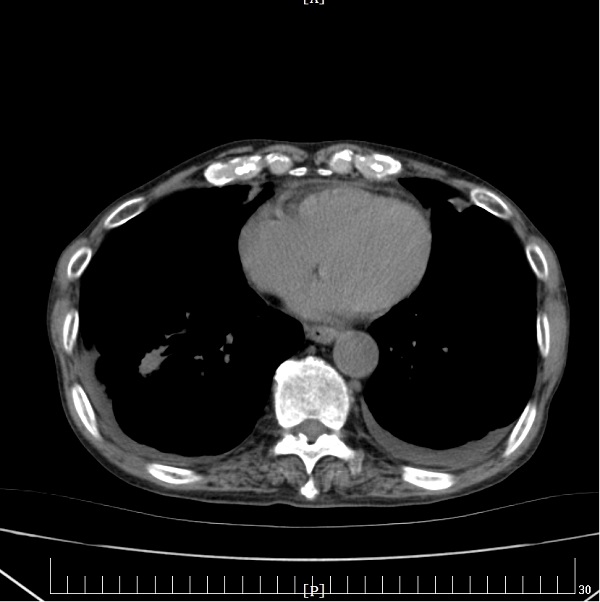

充分研究病情后,刘娟妮主任团队积极与家属沟通,对症治疗的同时,在CT引导下行经皮肺穿刺活检术,术后病理提示:中分化腺癌,基因检测结果提示:EGFR Exon19突变。明确诊断后,刘娟妮主任团队一边安慰患者及家属的情绪,一边对患者的全身状况及疾病进行了充分的评估,邀请相关科室会诊,经MDT讨论并结合患者目前症状、基因检测结果分析及国内外最新指南推荐,制定了个性化的治疗方案,给予口服三代靶向药控制肿瘤。治疗1个月后,复查头颅MRI及胸部CT,结果显示患者肺原发肿瘤、脑多发转移瘤较前均缩小、部分消失。

治疗前

治疗后